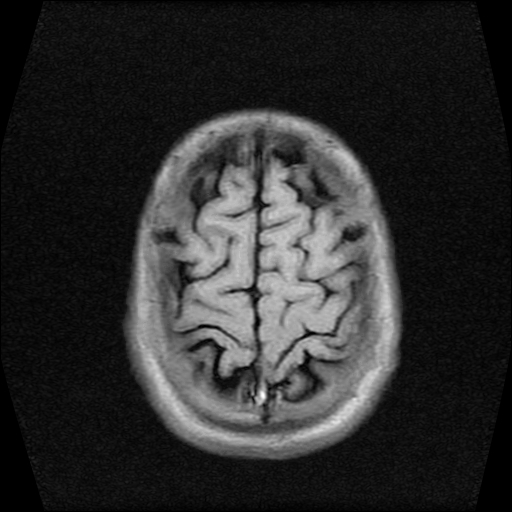

标题: MRI2584:静脉窦血栓?请会诊!

男性,39岁。头晕,视物模糊2月余。血压142/85。矢状窦内高信号有问题吗?

图片不全请提供。

t1wi像可以出现缓慢流速血管呈高信号,应加t2wi及mrv